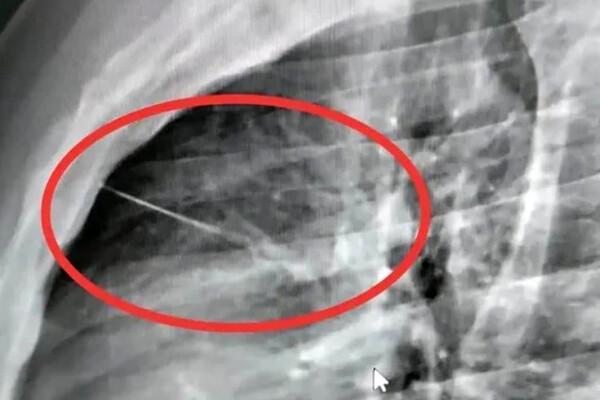

Рентген в местной больнице, куда сначала доставили тайца, показал острый посторонний предмет рядом с сердцем, позже медики установили, что это игла длиной около семи сантиметров. Пациента срочно перевели в крупную больницу Бурирама, чтобы провести высокорисковую операцию по удалению инородного тела.